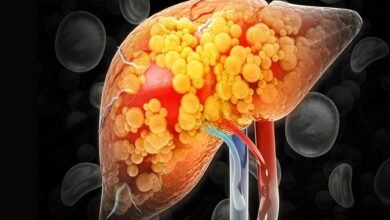

Fatty Liver के 5 लक्षण न करें नजरअंदाज! आंख और नाखून सबसे पहले बताते शरीर का हाल

डेस्कः आजकल की तेज़ रफ़्तार जिंदगी, खराब खानपान और कम शारीरिक गतिविधि की वजह से फैटी लिवर (Fatty Liver Disease) एक आम समस्या…